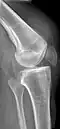

Operative image: 1. Kneecap 2. upper patella pole with drill holes 3. Stump of the quadriceps tendon